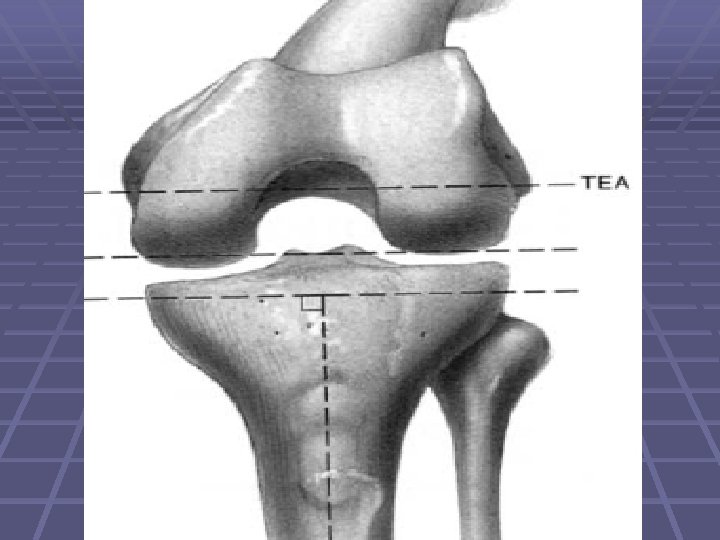

The Femoral Prep. Cont. § Rotation of the femoral component should be determined using the epicondylar axis

The Femoral Prep. § Bone defects on the femur generally are managed with metal augmentation § Small defects and larger defects can be filled with cement